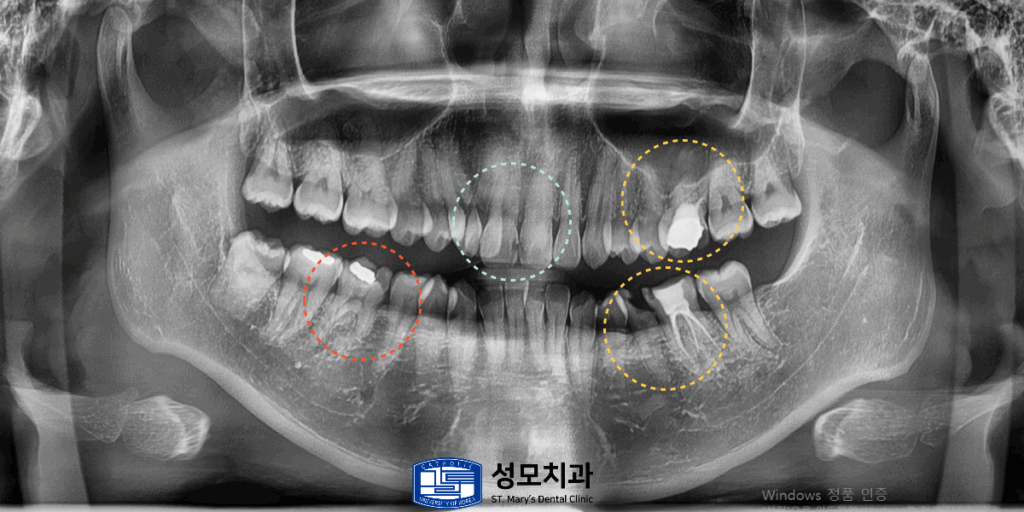

2. 치료 전 파노라마 사진

빨간색으로 표시된 오른쪽 아래 어금니에는

아말감 주변의 치질이 파절되거나 벌어져 있어서

2차 우식이 진행된 치아가 있었습니다.

3. 치료 계획 수립

왼쪽 위아래에서는 내부 코어까지만 형성된 상태로

최종 보철이 미완성인 치아 두 개가 확인되었는데요.

노란색으로 표시된 부분은 충치가 깊게 진행되어

치관이 약 3분의 1만 남아있었습니다.

파란색으로 표시된 상악 전치부 첫 번째 앞니의

사이 인접면에는 초기 우식과 변색이 동반되어 있었습니다.